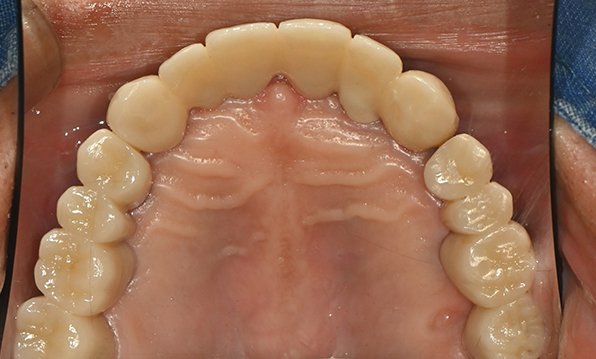

Case 01

Before After